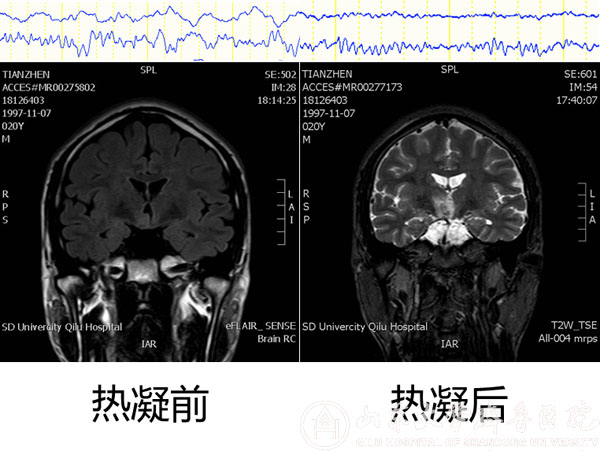

手术前后颅内脑电及MRI对比

该患者男,20岁,发作性头痛、痴笑、左眼向上凝视病史11年,口服丙戊酸钠、拉莫三嗪、鲁米那等多种抗癫痫药物效果欠佳,每日痫性发作仍3~6次,颅脑MRI提示右侧丘脑前下部占位性病变,考虑下丘脑错构瘤。患者收入我院功能神经外科病房后,赵秀鹤副主任带领神经内外科团队共同对患者进行了充分的术前评估,对手术方案进行了深入的讨论,考虑到病变位置重要且深在,开放性开颅手术风险高,术后并发症发生率高,最后决定采用立体定向脑电图引导下射频热凝术的治疗方案。10月21日,徐淑军主任、徐硕主治医师为患者制定了SEEG方案,并在手术机器人引导下成功将颅内电极埋藏在预设手术靶点。经术中CT、多模态影像融合技术以及立体定向脑电监测等多种手段验证靶点后,对致痫灶实施精准射频热凝。术后患者癫痫发作频率较术前减少,未见明显不良反应,已顺利出院,长期疗效正在随访观察中。

作为新兴的癫痫病灶诊断与定位技术,SEEG通过埋藏颅内电极的方式精准捕捉致痫灶起源并明确癫痫传播网络,为难治性癫痫的外科治疗提供依据,必要时还可通过电极热凝对位置较深、范围较小或位于功能区的病变进行毁损,发挥治疗作用。由于对定位精准度要求极高(以毫米计算),传统SEEG电极植入主要依靠立体定向框架系统,但手术操作繁琐,耗时较长,且需要在患者局部麻醉下安装立体定向头架,增加患者心理压力。神经外科手术机器人系统通过无框架定位技术与机械臂辅助,在保证手术精度的同时,简化SEEG手术过程,缩短手术时间,改善患者体验。本次手术是手术机器人系统在我院神经外科首次亮相。除SEEG外,未来机器人还有望应用于颅内病变活检、血肿穿刺引流、术中导航甚至脑深部电刺激器植入等神经外科手术。